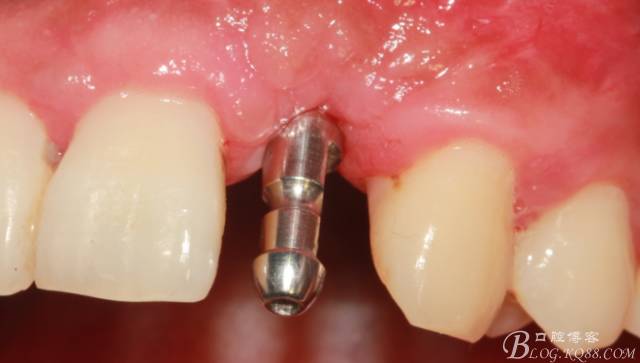

術(shù)后1個月

術(shù)后5個月